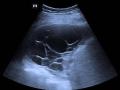

Ultrassom de tórax com derrame pleural multiloculado

Ultrassonografia na complementação do raio-x de tórax com suspeita de derrame pleural

Avaliação de hemitórax opaco à radiografia simples de tórax

Derrame pleural